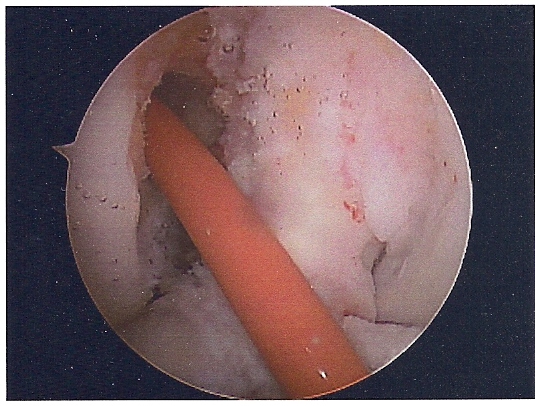

She had ACL replacement surgery on March 28th, using Bone-Patellar-Bone graft from her own patellar tendon. These are the images are scanned from pictures taken by the scope during the surgery. We were supposed to get a DVD of the procedure, but forgot to remind him on the day of the surgery. Oh well...

ROBINSON CATHETER